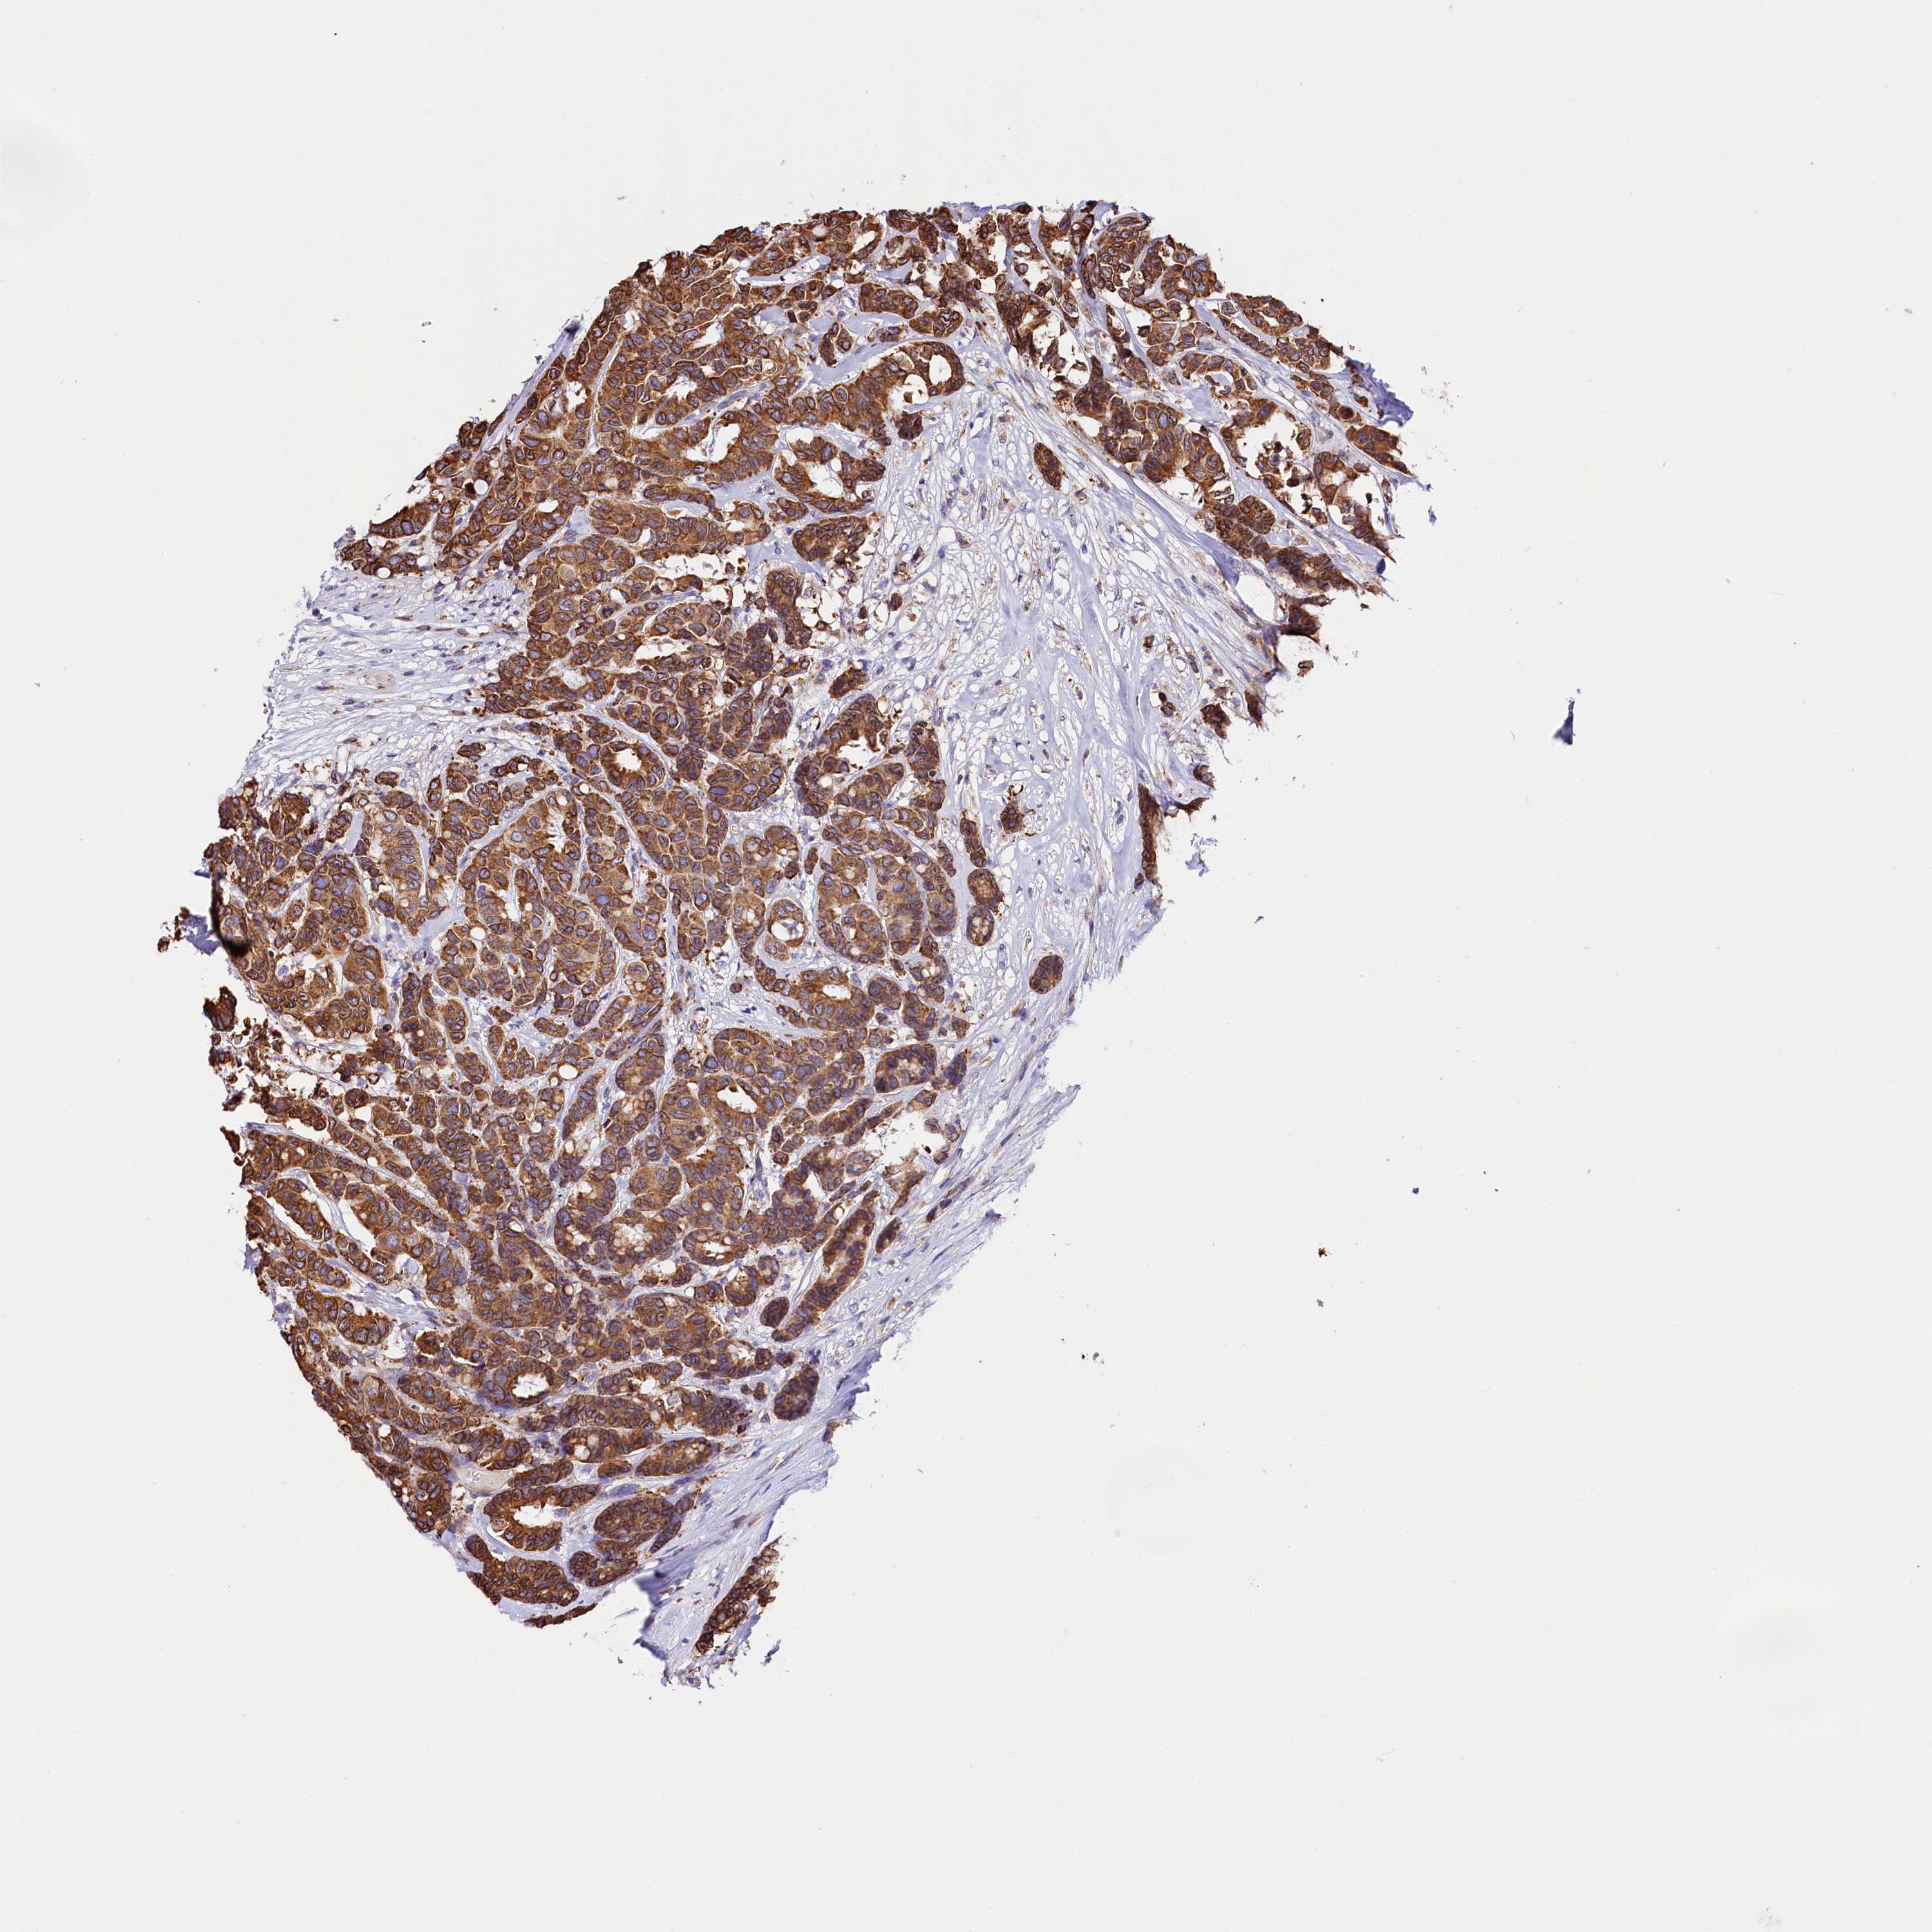

BRCA TCGA BRCA VALIDATION PROTEIN EXPRESSION

ANTIBODIES

AND

VALIDATION